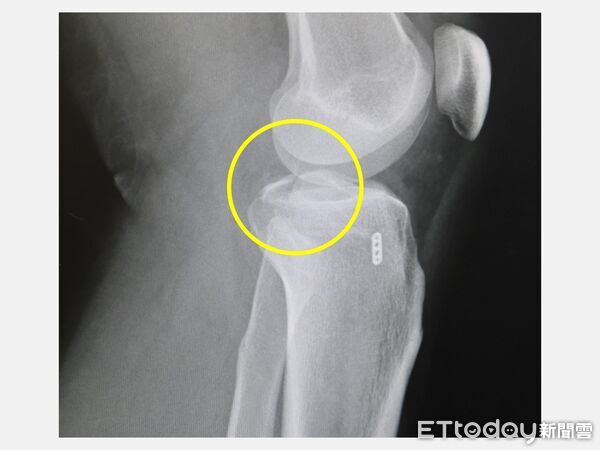

▲X光顯示,左膝脛骨後十字韌帶撕脫性骨折(圓圈處)。(圖/記者游瓊華翻攝)

這名黃先生是在騎機車上班途中發生車禍,送醫後初步X光檢查顯示膝關節骨折,進一步確認為「後十字韌帶撕脫性骨折」,屬於韌帶連同骨塊被拉離原位的複合型損傷。收治個案的骨科醫師徐振恆指出,台灣機車通勤人口龐大,交通事故中除了常見擦傷與骨折,膝關節韌帶損傷其實並不少見,其中後十字韌帶撕脫性骨折常發生在跌倒瞬間膝蓋彎曲、脛骨遭受向後撞擊時。

這類患者多半出現腫脹、疼痛、關節無力與不穩感,即使勉強撐拐杖也難以承重。若未及時診斷與治療,可能造成長期關節不穩,甚至增加日後退化性關節炎與功能障礙風險。醫師說明,傳統開放式手術須在膝後方切開超過10公分傷口,但該區域神經與血管密集,術中風險與術後復原負擔都較大,病患可能面臨肌肉萎縮、關節沾黏或僵硬等問題。